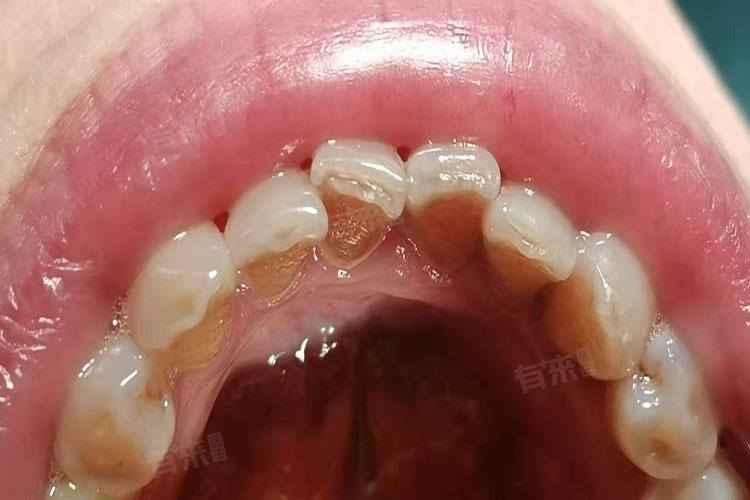

20岁出现牙结石属于不正常现象,通常反映了口腔卫生维护的不足或生活习惯的不良。牙结石即沉积在牙齿表面已经钙化的菌斑及软垢,形成与口腔卫生状况密切相关。在正常情况下,良好的口腔卫生习惯可以有效防止牙结石的形成。

- 牙结石的形成是一个复杂的过程,涉及口腔内细菌、食物残渣以及唾液成分等多种因素。当口腔卫生不佳时,食物残渣和细菌容易在牙齿表面聚集,形成牙菌斑。随着时间的推移,这些牙菌斑会与唾液中的矿物质结合,逐渐钙化形成牙结石。对于20岁的年轻人而言,如果已经出现牙结石,很可能意味着其口腔卫生习惯存在问题,如刷牙不彻底、饭后不漱口、长期使用含糖食物等。

- 牙结石的存在不仅影响美观,更重要的是会对口腔健康造成危害。它可能刺激牙龈,引发牙龈炎和牙周炎,导致牙龈出血、红肿、疼痛等症状。长期存在的牙结石还可能破坏牙周组织,造成牙齿松动甚至脱落。牙结石还可能引起口臭,影响个人形象和社会交往。